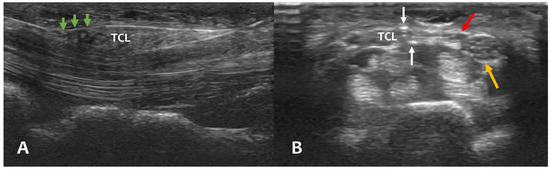

Long-Term Outcomes of Ultrasound-Guided Thread Carpal Tunnel Release and Its Clinical Effectiveness in Severe Carpal Tunnel Syndrome: A Retrospective Cohort Study

Ultrasound-guided thread carpal tunnel release (TCTR) was proposed as an effective and safe surgical technique with faster recovery and fewer complications. This study was conducted to confirm the long-term outcomes after TCTR and verify its clinical effectiveness in severe carpal tunnel syndrome (CTS) [...] Read more.

Ultrasound-guided thread carpal tunnel release (TCTR) was proposed as an effective and safe surgical technique with faster recovery and fewer complications. This study was conducted to confirm the long-term outcomes after TCTR and verify its clinical effectiveness in severe carpal tunnel syndrome (CTS) for more insights into TCTR procedure. A total of 168 TCTR procedures were performed in 152 individual patients by two physiatrists during 36-month period. In an assessment of 82 hands, surgical outcomes of 2 years after TCTR could be obtained, and the grade 6 CTS group of 21 hands, classified as extremely severe grade by Bland’s classification, was compared with other severity groups (grade 1–5). The Boston Carpal Tunnel Syndrome Questionnaire (BCTQ) was used to assess surgical outcomes. No adverse events occurred in all cases including the case of severe CTS and anatomical variants. TCTR showed significant improvement in BCTQ scale within 1–2 weeks, which continued up to 2 years with no recurrence (p < 0.01). Although slower and more progressive than the other severity group, there was also significant improvement relative to the BCTQ scale around 4 weeks after procedure in the grade 6 CTS group (p < 0.05). With the familiarity of ultrasound, ultrasound-guided TCTR is an effective and reliable surgical treatment for CTS in long-term outcomes and in severe CTS. Full article